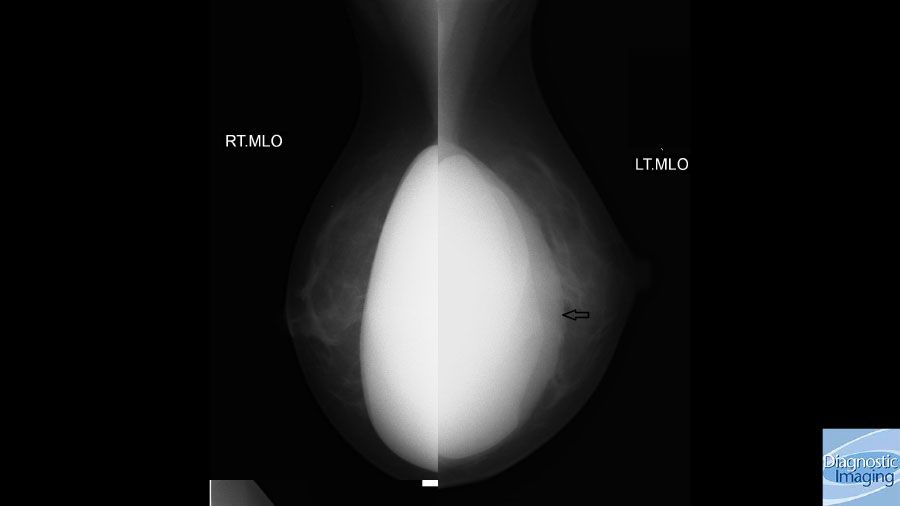

Case History: 28-year-old female with left breast pain and swelling two years after augmentation mammoplasty.

Case History: 28-year-old female presented with left breast pain, swelling, and hard feeling of her breast implant two years after augmentation mammoplasty.